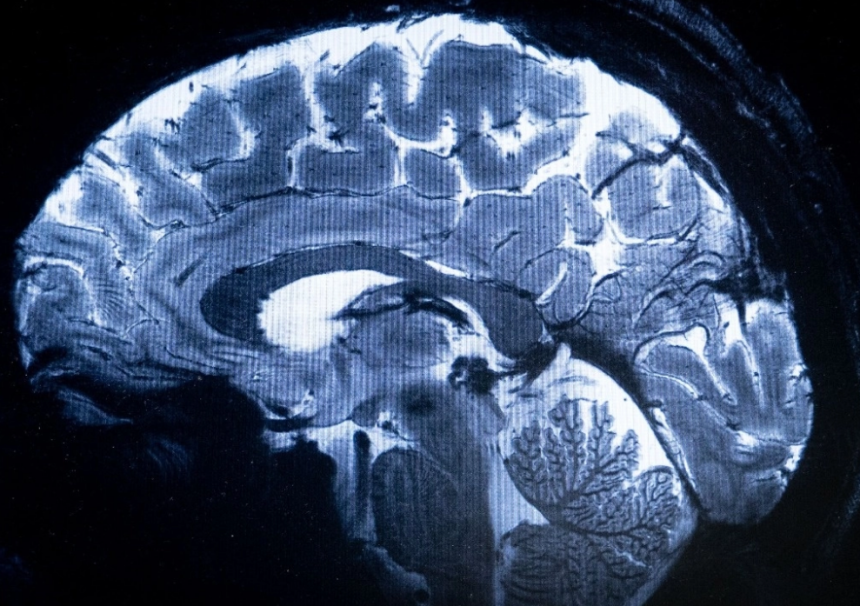

Saclay. El escáner de resonancia magnética (IRM) más potente del mundo ha logrado escanear con un nivel de precisión desconocido el cerebro humano, anunciaron sus responsables en Francia, una proeza que podría ser decisiva para detectar enfermedades.

Esta potencia permite que la máquina escanee imágenes 10 veces más precisas que los IRM comúnmente utilizados en hospitales, cuya potencia normalmente no supera los tres teslas.

En una pantalla de computadora, Vignaud comparó imágenes tomadas por este poderoso escáner, apodado Iseult, con las de un IRM normal.

“Con esta máquina podemos ver los pequeños vasos que alimentan la corteza cerebral, o detalles del cerebelo que eran casi invisibles hasta ahora”, dijo.